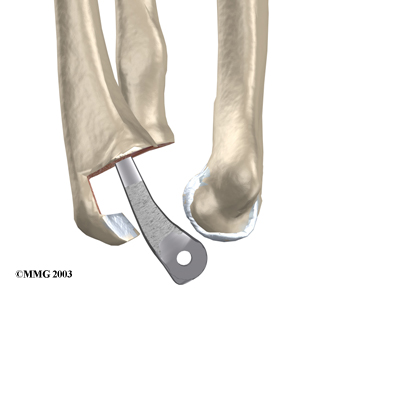

Each prosthesis has two parts. The humeral component replaces the lower end of the humerus in the upper arm. The humeral component has a long stem that anchors it into the hollow center of the humerus. The ulnar component replaces the upper end of the ulna in the lower arm. The ulnar component has a shorter metal stem that anchors it into the hollow center of the ulna.

The hinge between the two components is made of metal and plastic. The plastic part of the hinge is tough and slick. It allows the two pieces of the new joint to glide easily against each other as you move your elbow. The hinge allows the elbow to bend and straighten smoothly.

There are two different ways to hold the artificial elbow in place. A uses a special type of epoxy cement to glue it to the bone. The has a fine mesh of holes on the surface. Over time, the bone grows into the mesh, anchoring the prosthesis to the bone.